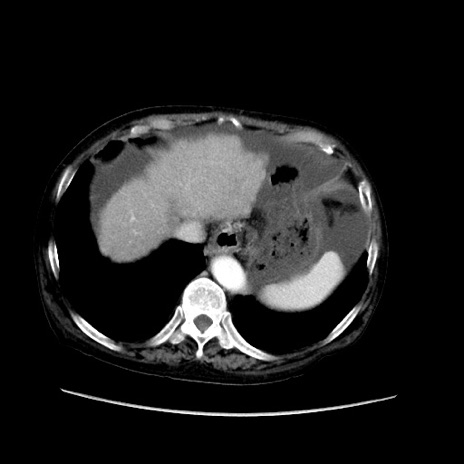

症例31(横断像)

【症例】80歳代 女性

【主訴】腹部膨満感

【現病歴】他院にて肝硬変にてフォロー中。1週間前から便秘、腹部膨満感、臍部腫瘤あり受診となる。

【既往歴】肝硬変

【身体所見】腹部膨隆あり、皮膚変化なし、疼痛なし。

【データ】WBC 4600、CRP 0.25